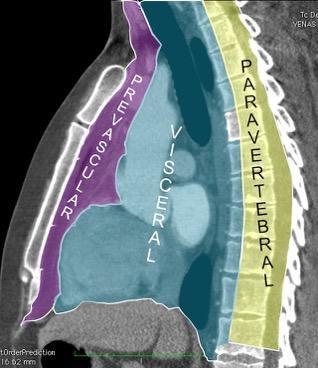

4. ANATOMÍA. ÁREAS DEL MEDIASTINO

5. ANATOMÍA. DIVISIÓN EN ÁREAS

6. ÁREAS DEL MEDIASTINO EN TC